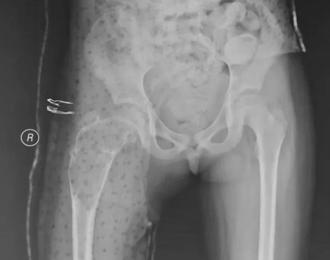

从影像学看,这个孩子手术后股骨近端留置多根钢针,术后2年左右的时间,尽管股骨强度有增加,但是骨囊肿还未愈合,并出现了部分退针的情况,孩子身高已经比第一次手术时长了近10cm了,选择什么样的治疗方案再次摆到面前,当我决定更换固定针,继续使用微创治疗理念时,患儿家长对于可能出现的针道激惹等并发症表示了完全的理解,并认真了解了术后相关的注意事项,正是因为家长的配合,手术之后患儿就能够进入快速康复。